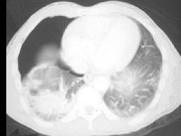

男,31岁,车祸后10小时余,请结合影像学检查,选出最可能的诊断 ( )A.肺癌B.肺结核C.气胸伴肺挫伤D.硅沉着病E.大叶性肺炎

问题 男,31岁,车祸后10小时余,请结合影像学检查,选出最可能的诊断 ( )

选项 A.肺癌 B.肺结核 C.气胸伴肺挫伤 D.硅沉着病 E.大叶性肺炎

答案 C